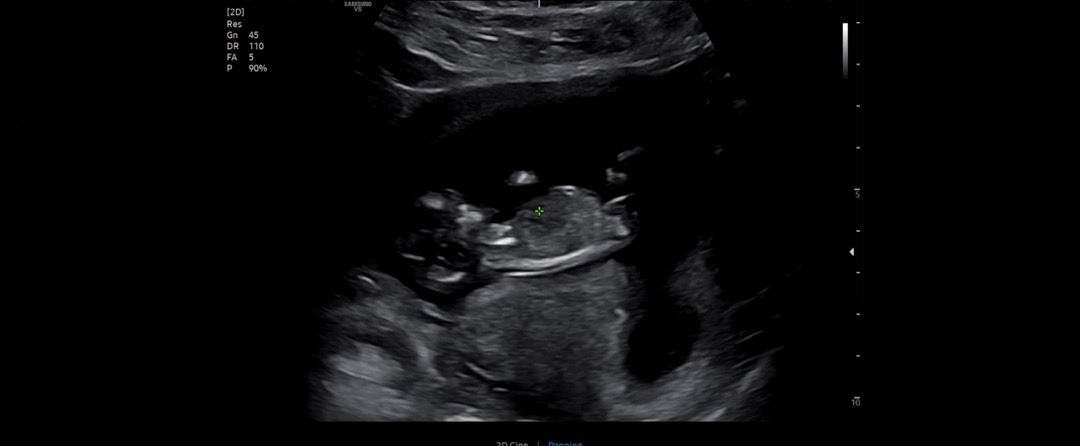

11주5일 각도법

오늘 1차 기형아검사 했는데 각도법 볼 수 있나요?